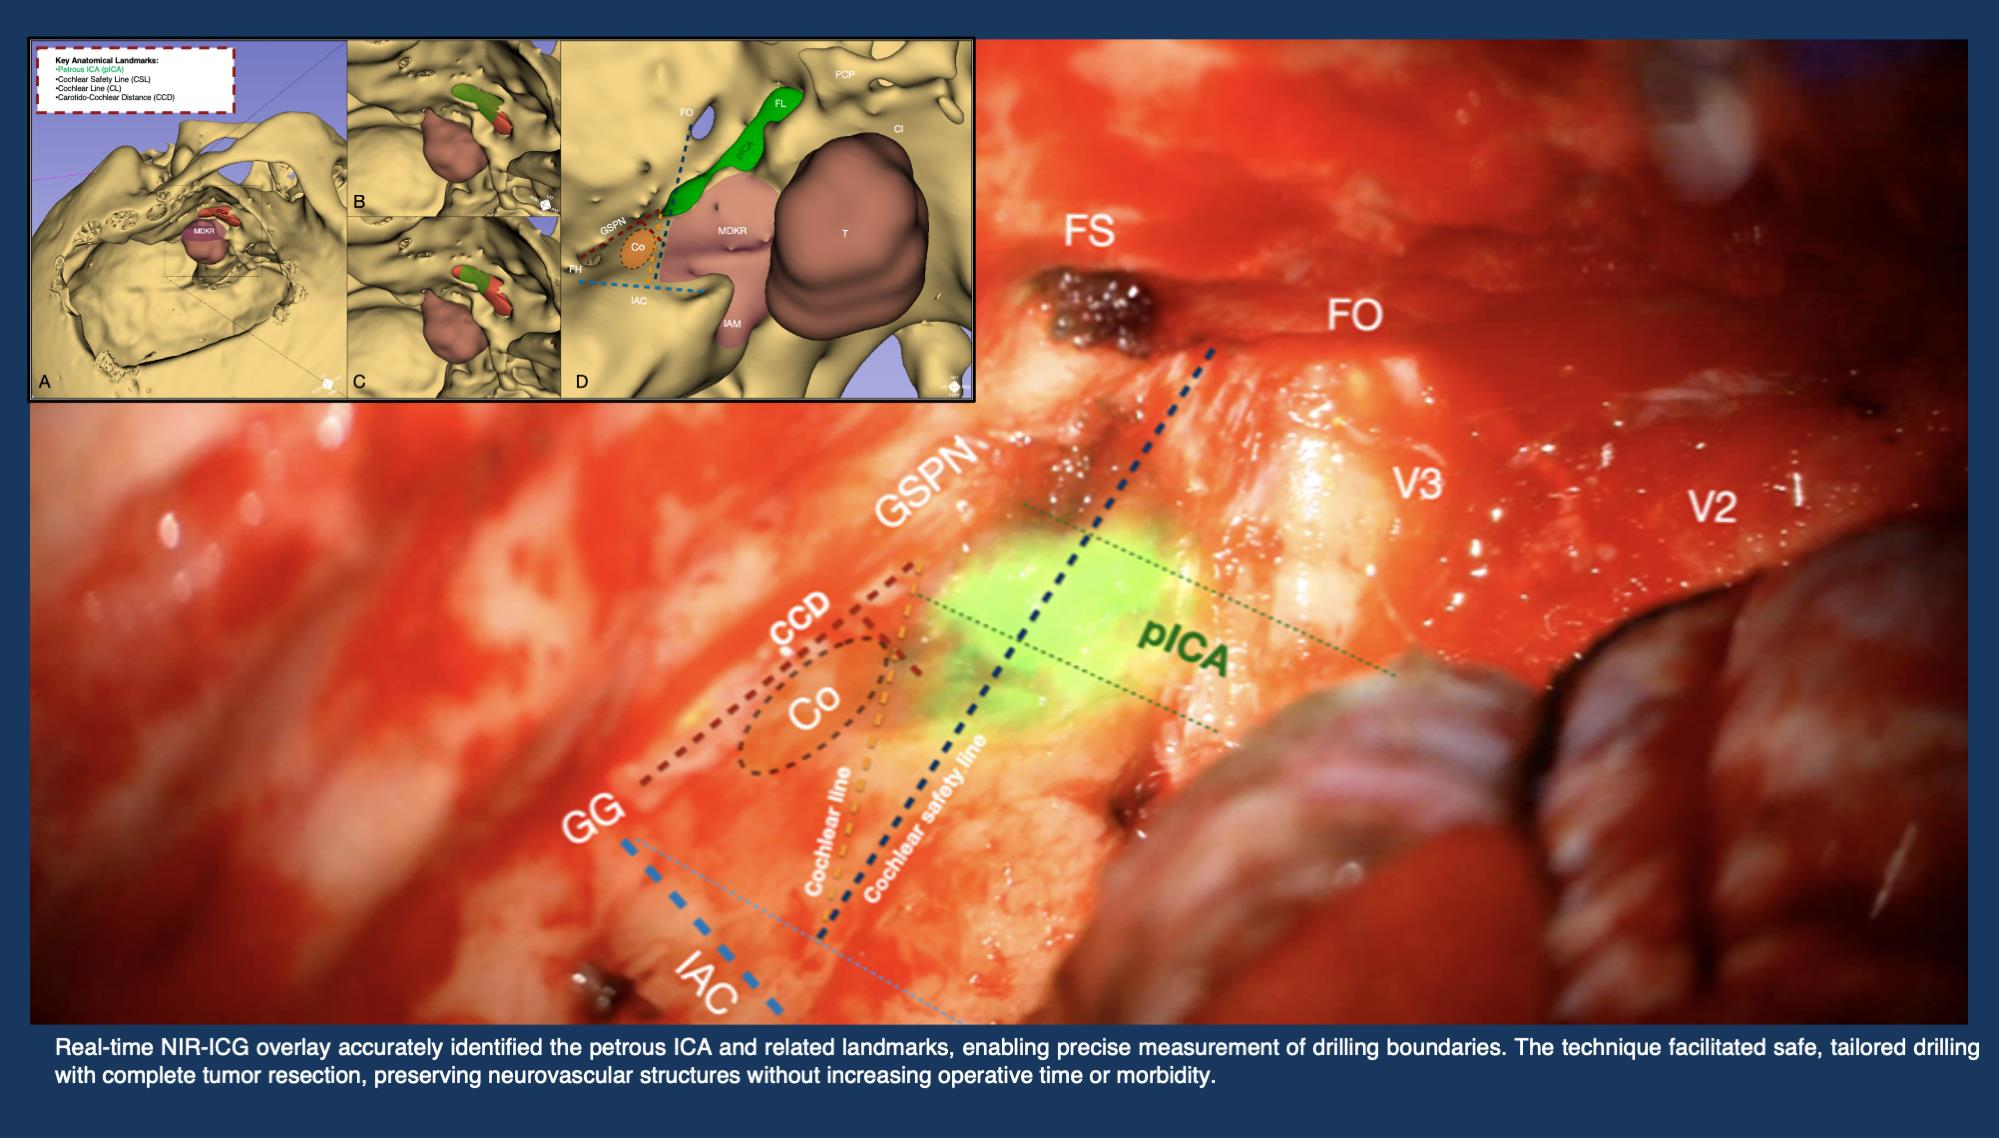

2.4. Anatomical Landmarks

- Cochlear safety line (CSL): Defined as the perpendicular line connecting the lateral rim of the foramen ovale to the transition fold between the roof and anterior wall of the internal acoustic canal (IAC). This line laterally delineates the cochlea [10].

- Petrous ICA (pICA): Identified using intraoperative ICGva.

- Cochlear line (CL): Projected perpendicularly from the petrous ICA–GSPN intersection (measured during ICGva) onto the IAC. This line marks the lateral position of the basal cochlear turn [11].

- Carotido-cochlear distance (CCD): Adapted from Dew et al., measured as the distance between the medial ICA wall (defined with ICGva) and the geniculate ganglion at the fallopian hiatus [12]. Probing through the hiatus or GSPN electrical stimulation with facial nerve EMG confirmation refined this measurement. A 7 mm distance from the geniculate ganglion crotch was designated the safest boundary for identifying the basal cochlear turn [12].

3.2. Surgical Application